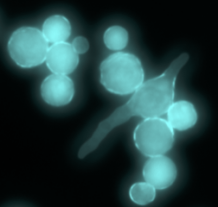

The fungus Rhizopus germinates and forms hyphae as part of the infection process.

The microscopic world resembles our world in some surprising ways. The environment around us is inhabited by microbes living in complex communities - some friendly and some not so friendly. Microbes compete with each other for resources and must also hide from or fight predators. One example of this is the fungus Rhizopus, which grows in the soil and on spoiled food and is the cause of "black fungus" outbreaks in covid patients.

In the soil, its predator is the amoeba Dictyostelium, a single celled microbe that can move through the soil and engulf Rhizopus, devouring it for nutrients. Scientists from the universities of Exeter and Birmingham found Rhizopus fights back against this predator by partnering with a bacteria called Ralstonia in a two way partnership. By living inside Rhizopus, Ralstonia hides from the predator. In return, Ralstonia makes a toxin that Rhizopus can use to neutralize the predator, preventing it from feeding on the pair.